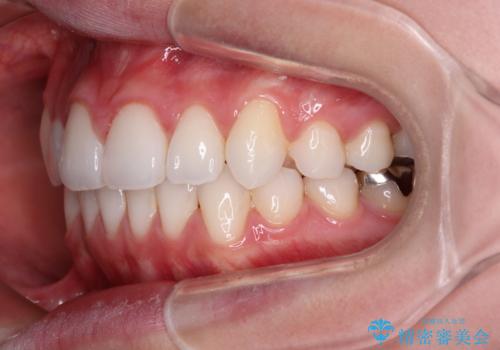

- 左右の八重歯を気にして来院された患者様です。

歯列としてはインビザラインでもワイヤー矯正でも対応できるものでしたが、インビザラインによる治療を希望されていました。

上顎の八重歯改善にインビザラインでは時間のかかってしまう可能性があり、更には口元が治療前よりも突出してしまう可能性があったため、補助装置により八重歯を事前に引き込んでおくことで、インビザラインによる治療をスムーズに行えるように計画しました。

補助装置を使用したことで、口元が突出することもなく、スムーズに仕上げることができました。